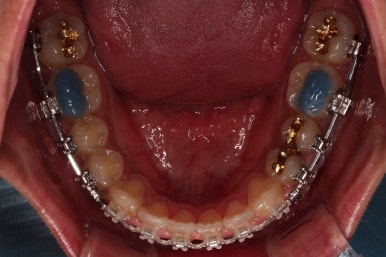

부산교정 장치를 부착했습니다.

이번에 선택하신 장치는 자가결찰 세라믹 장치에요. 스스로 철사를 묶는(결찰) 뚜껑이 달린(자가) 세라믹 성분의 장치인데요.

기능적으로도 우수하고, 세라믹이다 보니 미적으로도 장점이 있습니다.

이번 환자분은 엠파워 클리어라고 하는 장치를 사용했으며 흔히 아신느 클리피씨와 동일한 계열의 장치입니다.

장치 부착 직후의 느낌 참고해 주시고요.